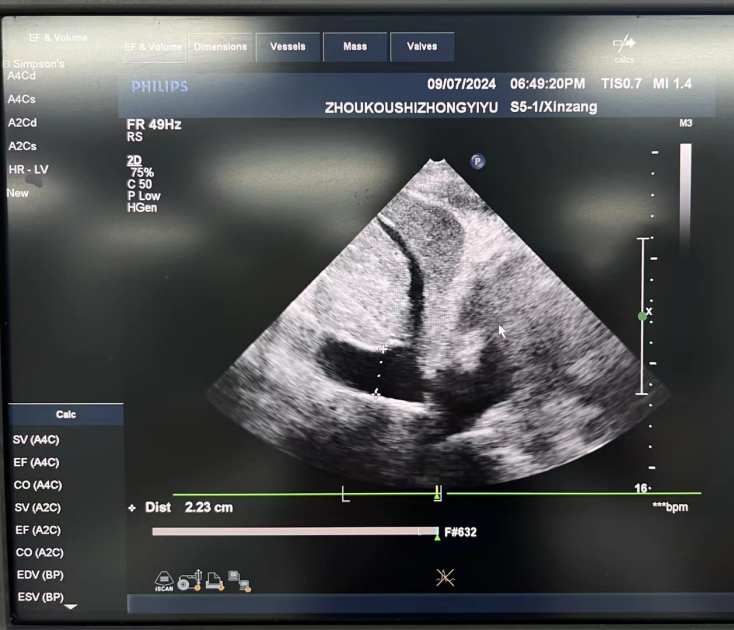

圖1:?流動(dòng)?學(xué)監(jiān)測(cè):下腔靜脈寬?,達(dá)2.2cm,?明顯呼吸變異度,提示?容量狀態(tài)(操作者:劉良麗)